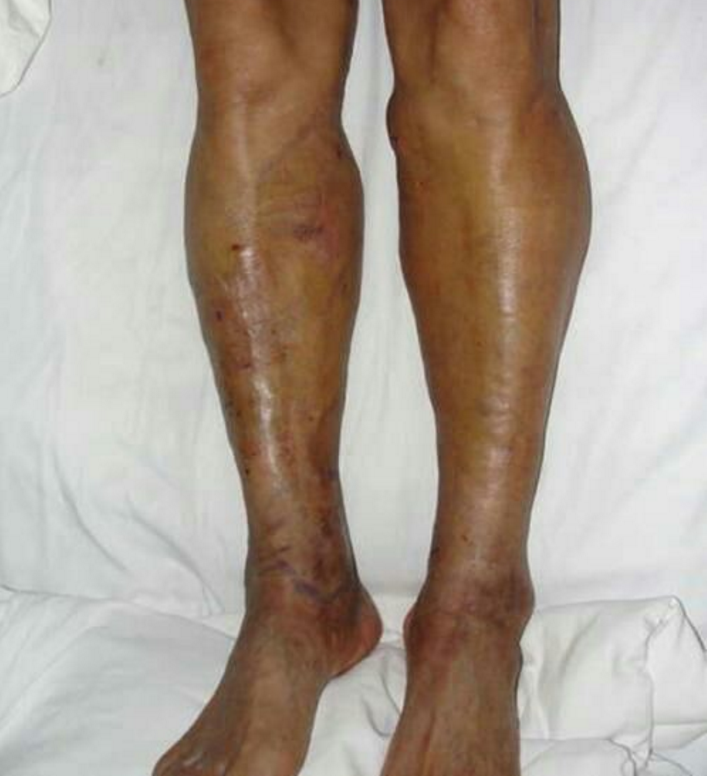

下肢靜脈曲張――微創(chuàng)介入硬化治療

下肢靜脈曲張X線造影圖像!像蚯蚓一樣在患者小腿之上縈繞!